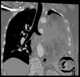

Lung torsion

The root of the lung is a group of structures that emerge at the hilum of each lung, just above the middle of the mediastinal surface and behind the cardiac impression of the lung. It is nearer to the back (posterior border) than the front (anterior border). [Source: Wikipedia ]